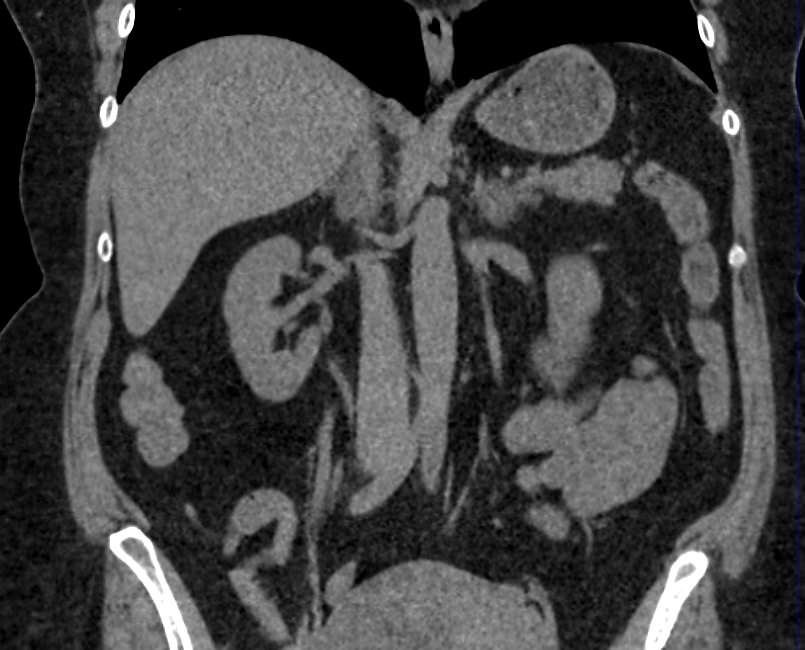

Мультиспиральная компьютерная томография (МСКТ) брюшной полости относится к современным лучевым методам исследования, с помощью которого можно оценить состояние органов брюшной полости (печени, желчного пузыря, поджелудочной железы, селезенки), прилегающих к ним кровеносных сосудов и лимфатических узлов.

С помощью мультиспиральной компьютерной томографии проводятся послойные рентгеновские снимки исследуемой области с толщиной среза от 0,5 мм. В нашей клинике исследование выполняется на компьютерном томографе экспертного класса TOSHIBA AQUILION CXL, который оснащен 128 детекторами, позволяющими получать за несколько секунд снимки брюшной полости с высокой точностью. Большое количество детекторов позволяет получить точные данные, при этом сократить время исследования и сделать минимальной лучевую нагрузку на пациента. Кроме того, инновационные технологии аппарата дают возможность сформировать объемную модель органа и окружающих структур, что также способствует проведению точной и достоверной диагностики.

При подозрении на опухоли, воспалительные процессы, гнойные очаги назначается КТ брюшной полости с внутривенным болюсным контрастированием. Для этого пациенту внутривенно вводится рентгеноконтрастное вещество на основе йода. Благодаря усиленному кровоснабжению препарат накапливается в структуре патологических образований и помогает врачу-рентгенологу выявить изменения в структуре внутренних органов.

Метод контрастирования помогает максимально точно выявить очаг патологии уже на начальной стадии, а также установить его локализацию, точные размеры, форму и особенности кровоснабжения.